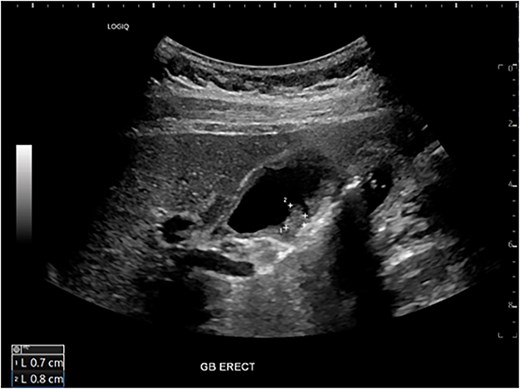

A 54-year-old female with a recent diagnosis of IBD complicated by PSC, presenting with right upper quadrant pain, underwent abdominal ultrasound, and magnetic resonance cholangiopancreatography (MRCP) as part of her PSC workup. Ultrasound demonstrated two 7 mm gallbladder polyps, with a normal gallbladder wall. MRCP demonstrated segmental intrahepatic duct dilatation in segments II and VIII in keeping with PSC (Fig. 1). Initial liver function tests and Ca 19.9 level showed only a mildly elevated GGT and ALP. Due to the recent diagnosis of IBD and small size of gallbladder polyps, observation with progress imaging at 12 months was undertaken. Repeat MRCP demonstrated a slight outpouching of the wall of the gallbladder with subtle enhancement of the lateral wall, with no concerning features for malignancy.

Magnetic resonance imaging liver/MRCP demonstrating subtle intrahepatic biliary dilatation (arrows), most pronounced in segment 8.